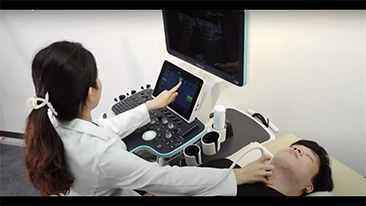

Meno stetoscopio e pi├╣ ultrasuoni?

L'ottimizzazione dei flussi di lavoro in ambito ostetrico e ginecologico ├© necessaria per completare grandi volumi di visite di screening per la salute delle donne. Ad esempio, le malformazioni del sistema nervoso centrale (SNC) sono una delle anomalie congenite pi├╣ comuni. A causa di varie circostanze che limitano l'accuratezza delle immagini, come la posizione poco adeguata del feto, l'MSP ├© particolarmente difficile da rilevare tramite l'ecografia 2D. Pertanto, il rilevamento e le misurazioni automatizzate possono migliorare notevolmente l'efficienza della scansione.